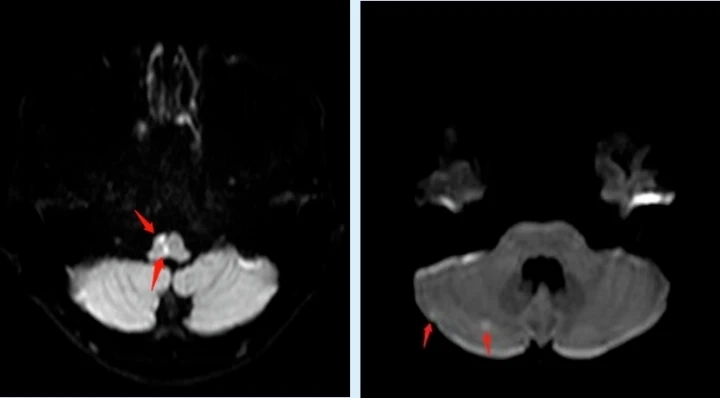

不久前,高三在讀學(xué)生小黃在課間休息時(shí)突然感覺(jué)自己左側(cè)肢體麻木、乏力,走路搖搖晃晃的,班主任見(jiàn)狀立即呼叫120送至惠州市第一人民醫(yī)院神經(jīng)內(nèi)科就診,出乎所有人的意料,平時(shí)生活作息規(guī)律、飲食均衡、熱愛(ài)運(yùn)動(dòng)且年僅17歲的小黃竟然得了“中風(fēng)”!頭顱MR顯示延髓、右側(cè)枕葉及右側(cè)小腦半球多發(fā)腔隙性腦梗死。